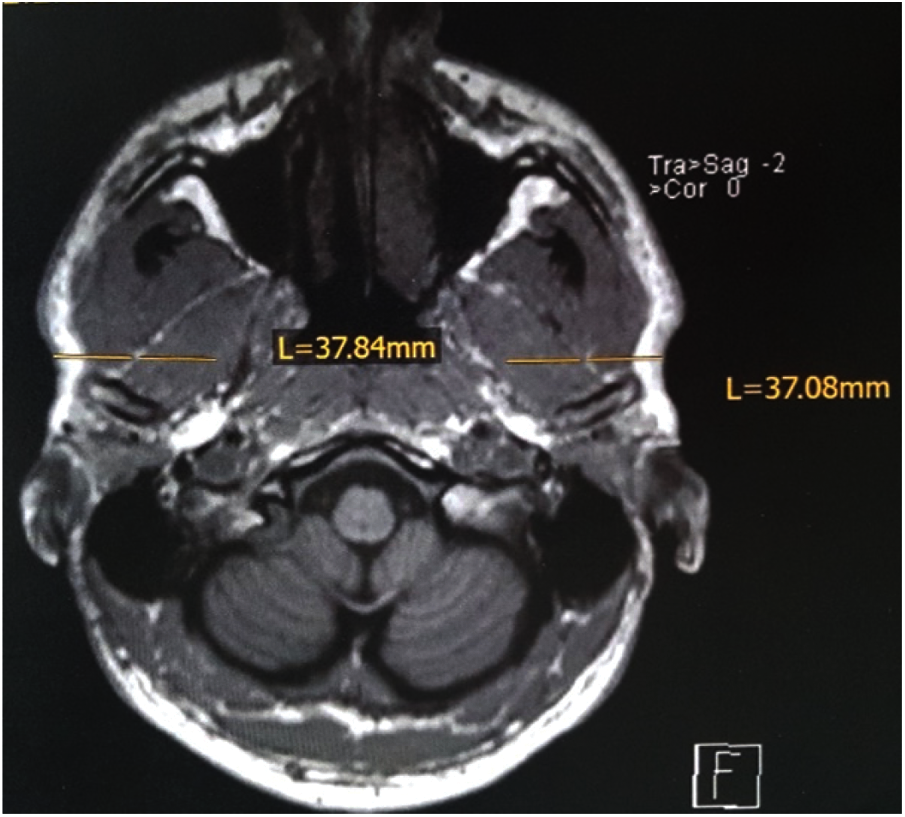

By the aid of MRI tomograms, which had been individually prepared for each test person at the Institute for Diagnostic and Interventional Radiology at the University Hospital of Würzburg, Germany, the penetration depths and penetration directions for the intramuscular fine wire electrodes were precisely determined, thus ensuring the exact final localization of the electrodes. An example of the measurements from an MRI layer (here pterygoideus lateralis) is shown in Fig. 2.

Figure 2: Example of measurements of penetration depth on the transverse plane of the skull MRI, for the pterygoideus lateralis muscle